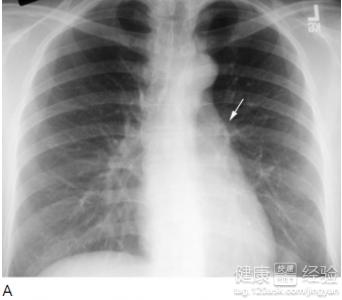

间质性肺炎x线图片,间质性肺炎x线

1x线胸片检查,ct扫描一般情况通过x线胸片检查,间质性肺炎晚期较容易

间质性肺炎x线

间质性肺炎胸片

间质性肺炎图片

间质性肺炎影像学